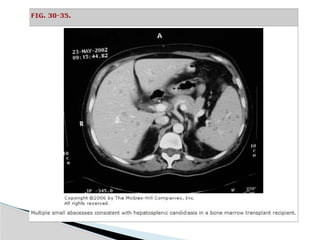

Computed Tomographic Scan

(Sensitivity 95%-100%)

 Well-demarcated areas hypodense to the

surrounding hepatic parenchyma.

 Peripheral enhancement is seen when IV contrast is

administered.

 Gas can be seen in as many as 20% of lesions.

 CT scan is superior in its ability to detect lesions less

than 1 cm.

 This technique also enables the evaluation for an

underlying concurrent pathology throughout the

abdomen and pelvis. Indium-labeled WBC scans are

somewhat more sensitive in this regard.

• #22 In an immunosuppressed patient who has multiple abscesses, hepatosplenic candidiasis should be considered, as well as more conventional pyogenic etiologies (Fig. 30-35).